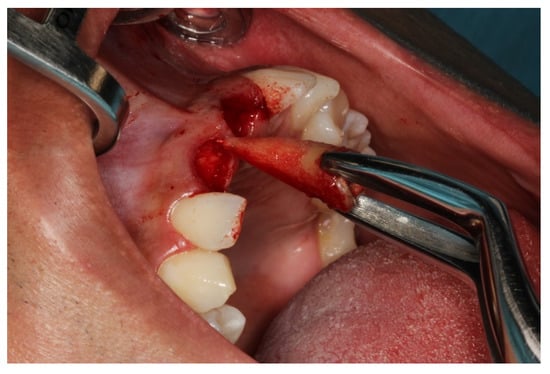

2.5. Surgical Procedures